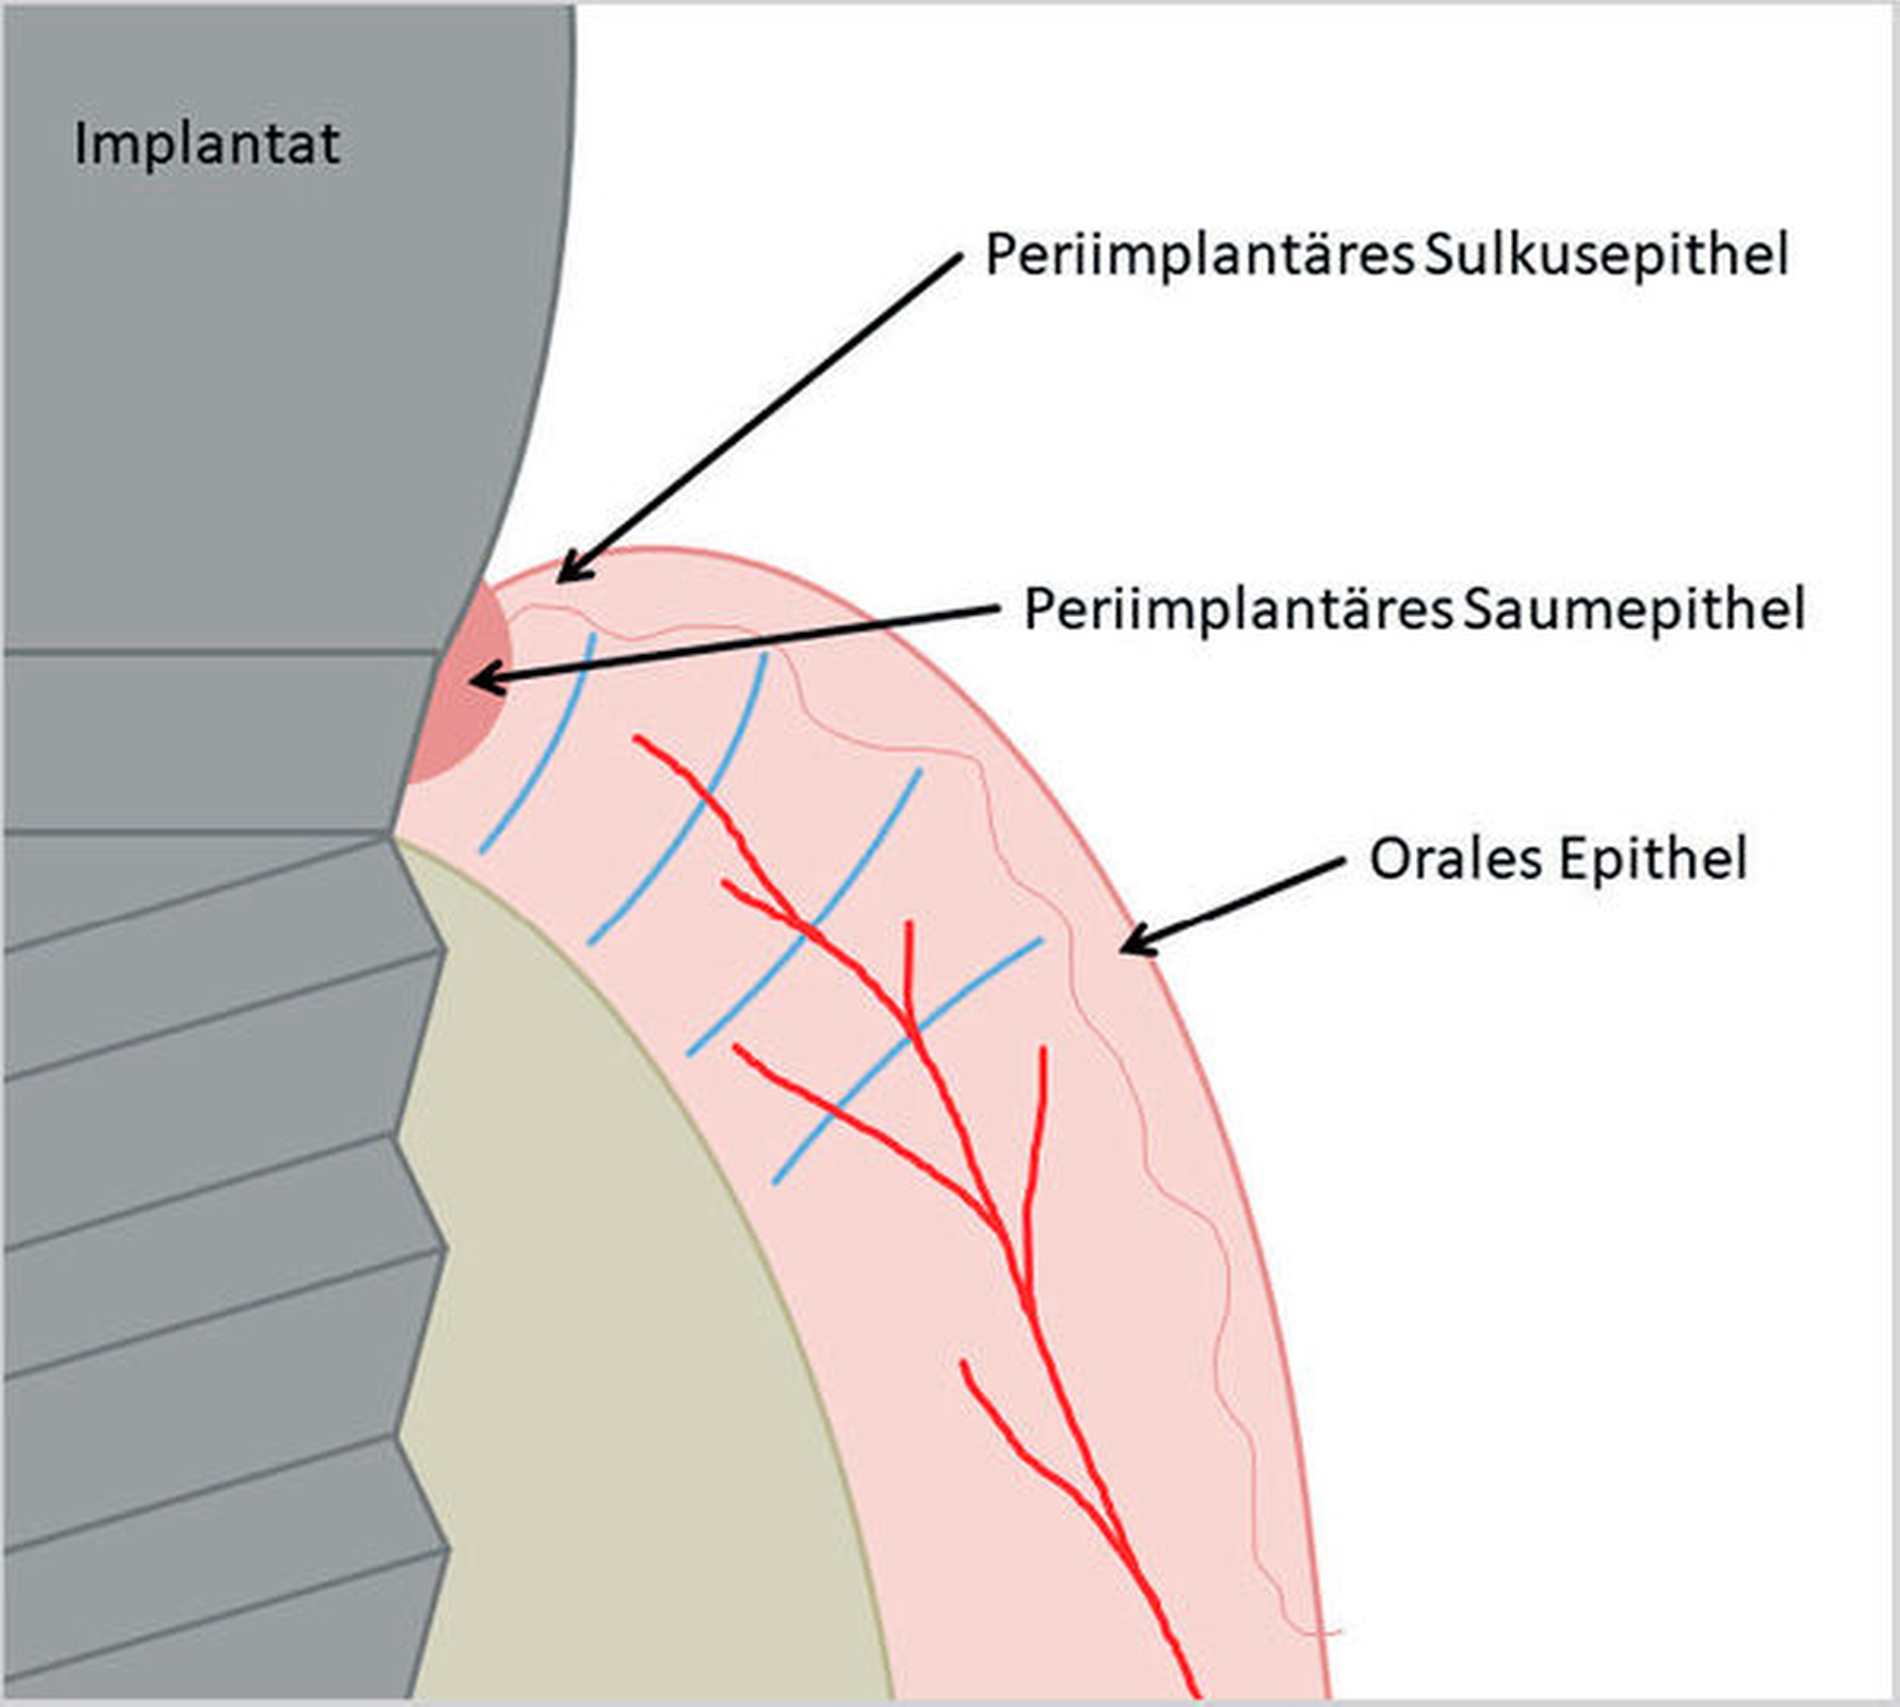

Nach Implantation heilt das dentale Implantat idealerweise ossär ein. Es bildet sich eine Knochen-Implantat-Verbindung aus – eine direkte strukturelle und funktionelle knöcherne Anlagerung an die synthetische Oberfläche des belasteten Implantats [Albrektsson et al., 1981; Albrektsson et al., 1986; Schroeder et al., 1976]. Diese Verankerung ist als Osseointegration bekannt [Branemark et al., 1969; Branemark et al., 1977]. Die periimplantäre Gesundheit ist definiert als klinisch gesundes Hart- und Weichgewebe um ein osseointegriertes Implantat. Dabei kann dies lediglich durch die Abwesenheit klassischer Entzündungszeichen beurteilt werden. Dazu gehören die Abwesenheit von Schwellung, Blutung auf Sondierung und Rötung des periimplantären Weichgewebes [Berglundh et al., 2018].

Kommt es jedoch zur Ausbildung einer Inflammation periimplantärer Gewebe ohne Knochenverlust, spricht man von einer periimplantären Mukositis. Wichtigstes Kennzeichen sind dabei die Blutung auf Sondierung und die Begrenzung der Entzündung auf das periimplantäre Saumepithel [Berglundh et al., 2018]. Breitet sich der pathologische Prozess in den Bereich des knöchernen Attachments aus, ist die Destruktion irreversibel und man spricht von einer Periimplantitis (Abbildung 1a). Zusätzlich zu den bereits genannten klinischen Kennzeichen kann man hier auch röntgenologisch den Knochenverlust feststellen, der mit erhöhten Sondierungstiefen und/oder Rezessionen einhergeht [Berglundh, 2019] (Abbildung 1b).